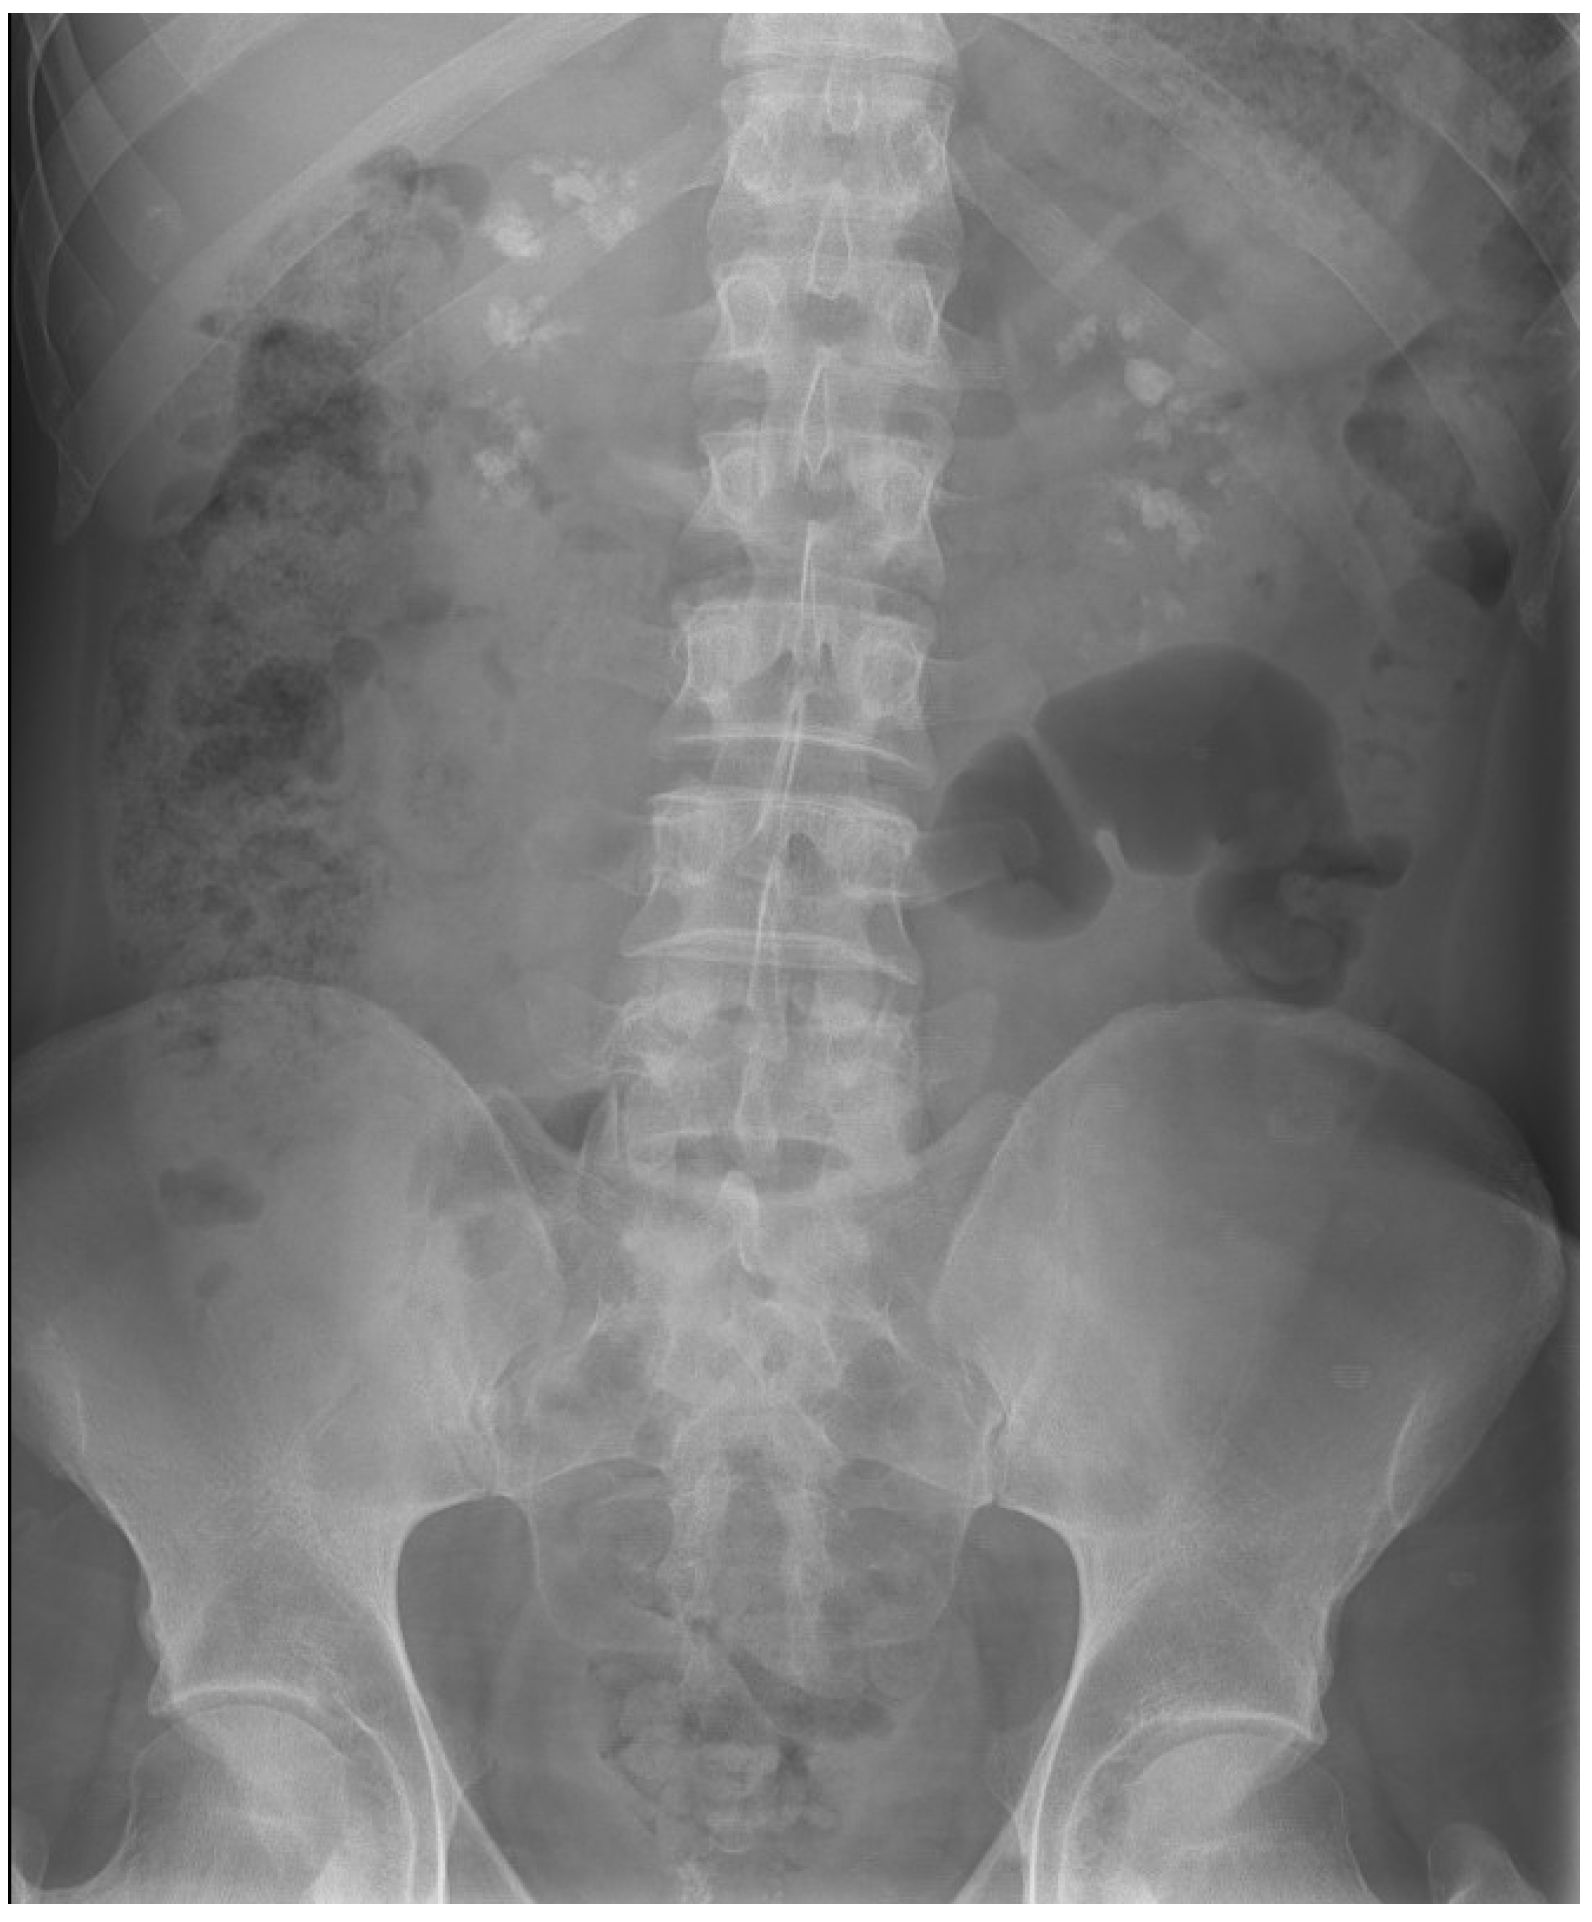

The prevalence of urinary lithiasis is progressively increasing, and it is estimated that approximately 5–10% of the general population will present lithiasis at some point in their lives [18]. According to the series studied, up to 11% of kidney stones in adult patients and up to 30% in children have a monogenic origin [8,19]. In DD, concomitant hypercalciuria and kidney stones appear to be more frequent in CLCN5 mutations [12], and hypophosphatemia and hyperphosphaturia are considered independent risk factors for the development of kidney stones and nephrocalcinosis [20]. In our patients, the kidney stones are predominantly composed of calcium phosphate. Four of the six patients developed kidney stones despite undergoing various procedures such as URS, RIRS, ureterolithotomy, ESWL, or ECIRS (Figure 1 and Figure 2), while two remained free of kidney stones at their last radiological follow-up (cases 3 and 5). One patient (case 3) has not had kidney stones during the course of the disease; however, he suffers severe nephrocalcinosis (Figure 3), which has led to end-stage CKD.

Figure 3.

Medullary nephrocalcinosis pattern in case number 3.